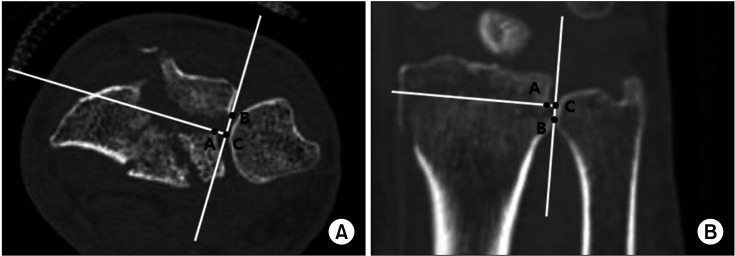

背景:创伤后骨关节炎(OA)是桡骨远端骨折(DRFs)的并发症之一。累及乙状窦切迹(SN)是一个危险因素,但很少有研究支持这一点。在本研究中,我们假设SN受累会影响手术治疗的DRFs的放射学和临床结果,并且根据SN受累程度的不同会有差异。方法:作者回顾了在我院接受手术治疗的DRF患者,并进行了超过5年的随访。根据SN受累情况将患者分为两组。所有患者在最后一次随访时均接受术后x线平片检查,以评估远端尺桡关节(DRUJ)创伤后骨性关节炎。在SN受累组的计算机断层扫描(CT)上,测量关节台阶和间隙距离。使用Knirk和Jupiter放射学标准对创伤后骨关节炎进行分级。临床评估方法包括握力、手腕活动度、疼痛视觉模拟量表评分、手臂、肩部和手部残疾问卷以及改良梅奥手腕评分。结果:放射学上,SN受累组的DRUJ OA评分明显更高。CT扫描测量的台阶距离和间隙距离显示与分级无显著相关性。两组临床结果无显著差异。结论:在至少5年的随访中,SN受累对DRF患者的临床结果没有影响。然而,放射学上,骨性关节炎分级明显高于SN受累组。因此,在伴有SN累及的DRF病例中,临床结局无明显差异,但有必要向患者说明,未来可能发生创伤后DRUJ关节炎。

Methods: The authors reviewed patients who underwent surgical treatment for DRF at our institution and were followed up for over 5 years. The patients were divided into 2 groups based on SN involvement. All patients underwent postoperative plain radiographs at the last follow-up to evaluate posttraumatic OA at the distal radioulnar joint (DRUJ). On computed tomography (CT) scans of the SN involvement group, articular step-off and gap distance were measured. Posttraumatic OA was graded using the Knirk and Jupiter radiographic criteria. For clinical evaluation, grip strength, wrist range of motion, pain visual analog scale score, Disabilities of the Arm, Shoulder, and Hand questionnaires, and Modified Mayo Wrist Score were assessed.